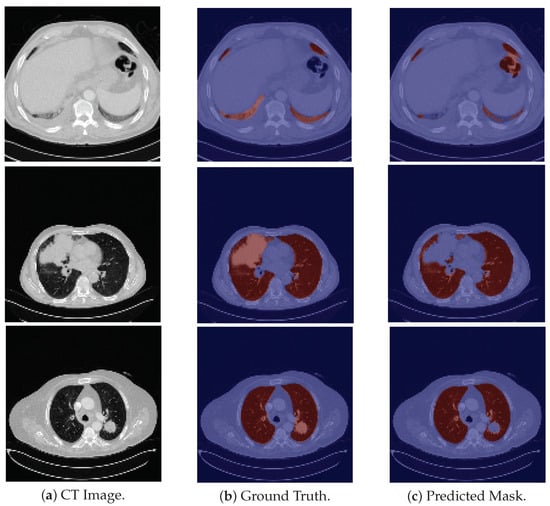

As for the CHUSJ dataset, the model demonstrates, once again, a difficulty in the segmentation of the base of the lung (see the first row of Figure 5). Nonetheless, what contributes most to the decrease in the DSC is the large masses of higher density that are present in the majority of the scans and which the model does not identify. The model correctly segments the surrounding pulmonary tissue and these masses are the only structures that are not included in its predicted masks. Examples of these scans are depicted in the last two rows of Figure 5.

In areas of higher density (“whiter” on the CT image) than the surrounding lung, resulting from involvement by interstitial lung disease or inflammatory/infectious pathology, they are not recognized by the model as lung tissue (see first three rows in Figure 6), although they corresponded to areas of “diseased” lung, involved by interstitial pathology.

In the case of lung neoplasms, something similar happens: the whole healthy lung is properly recognized; however, only the area of the lung mass, which is denser (“whiter”) than the remaining lung, is not properly recognized (see last two rows in Figure 5).

A similar situation occurs in areas of the lung that are even less dense than usual (“blacker” on the CT image) which may also correspond to areas of “diseased” lung, in this case, areas of “air-trapping”, emphysema, etc. (see the last row in Figure 6).

Figure 6. Examples from HUG-ILD dataset. First three rows show cases with higher density that the model does not classify as being lung tissue. Last row shows a darker pulmonary region misclassified by the model.

Figure 5. Examples of CHUSJ images, the ground truth and predicted mask. The first row is an example in which the model fails to correctly segment the pulmonary base; and second and third rows are examples in which the model does not segment the high density tumor masses.